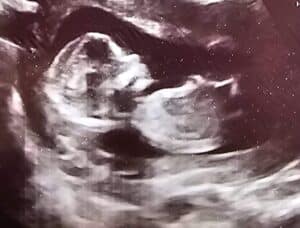

Not only have my PTLS symptoms went away, I’m carrying a healthy baby boy!

From the bottom of my heart, thank you for helping us grow our family.